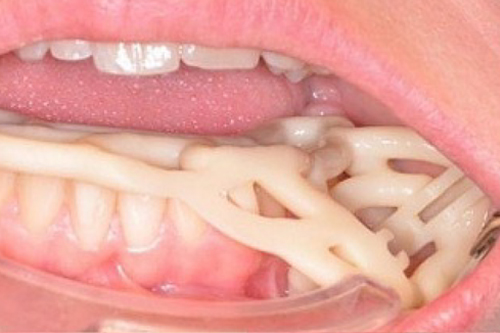

新一代口腔种植导板

西泰克双导(TwinGuide)数字化种植辅助系统,利用自研的TG-System系统、TG-Design设计软件、结合TG-Ai系统和设计团队为牙医提供安全可靠的种植方案,并通过3D打印生成产品。

双引导更精准

术野更开阔

冷却更充分

西泰克双导(TwinGuide)数字化种植辅助系统,利用自研的TG-System系统、TG-Design设计软件、结合TG-Ai系统和设计团队为牙医提供安全可靠的种植方案,并通过3D打印生成产品。